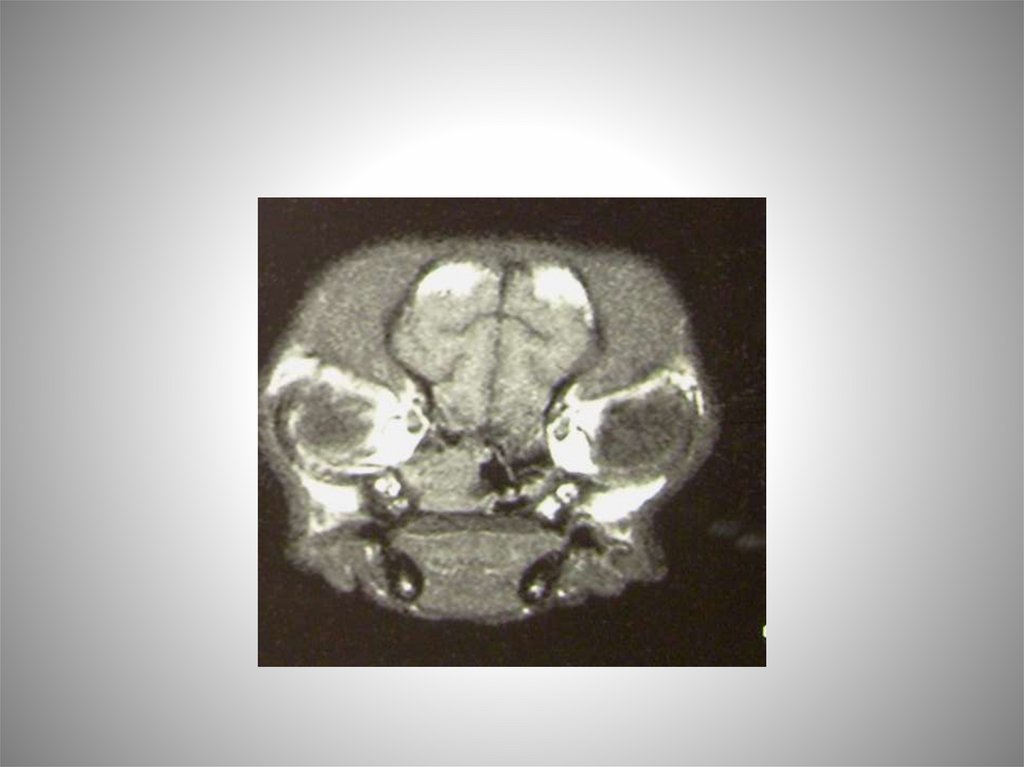

Клинический случай.

Японский хин 2 года Сеня.

Анамнез:

У животного в течении длительного времени

наблюдалось затрудненное дыхание с

прогрессией. Слизистые, а затем слизистогнойные выделения из полости носа.

Проходили лечение в других клиниках с

диагнозом гнойный ринит, но состояние

ухудшалось. Периодически начались

односторонние кровотечения.

МРТ-диагностика